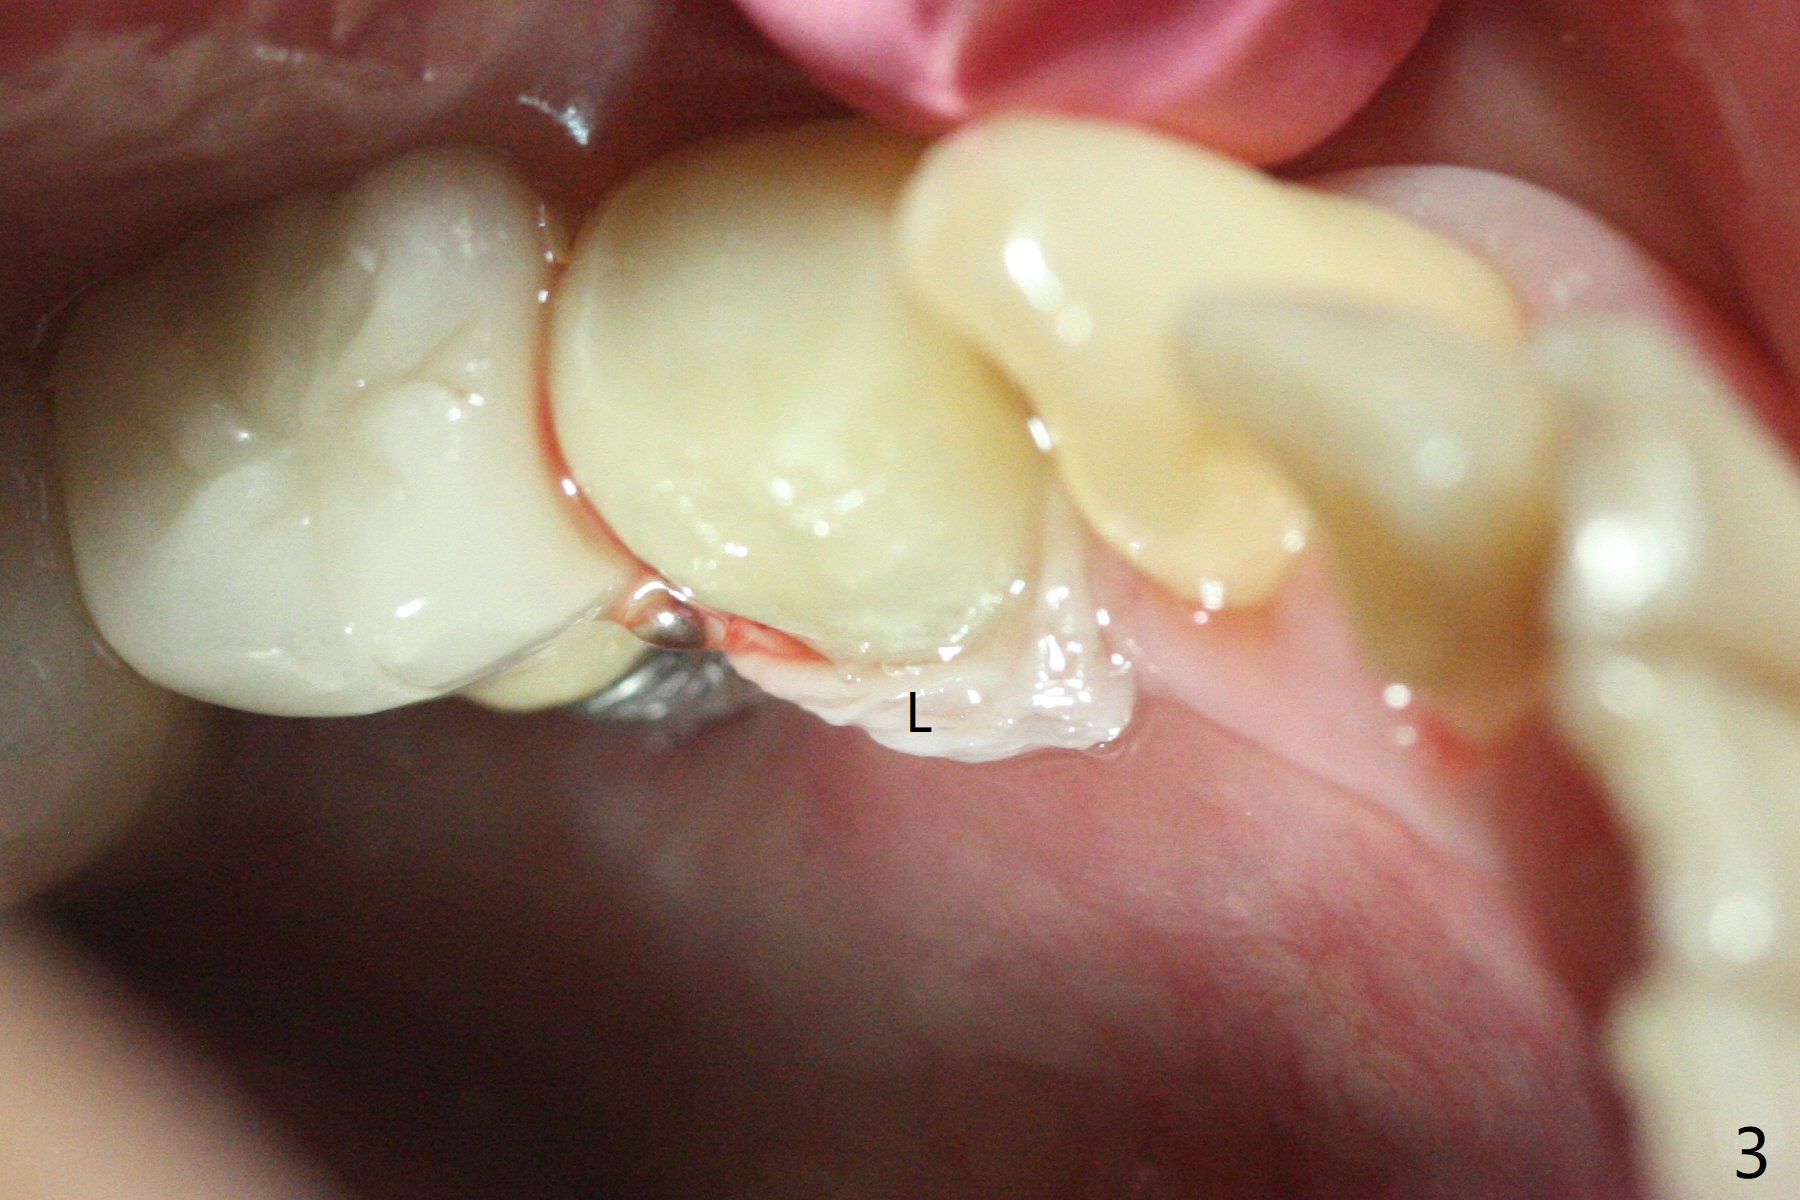

尽管使用导板,钻洞也不快,左下4植体仍旧偏移远中(图一)和颊侧(颊侧间隙比预计小),原因:斜面(图一:箭头),骨质硬,周围牙冠射线折射,导板就位前必须磨第二前磨牙近中面(今后遇到这些情景,选择徒手种植)。庆幸的是牙槽嵴水平两个植体还不是最接近(与根尖相比),粘性植骨(图一:*)但愿能缓解术后骨质吸收。制作临时牙冠后(图二:P),将PRF(图二:^;三:L(舌侧))插入牙冠和骨粉之间。术后六天软组织愈合正常(图四)。术后4个月远中牙槽嵴稍微下降(图五:*)。由于基台偏向远中,为了防止牙冠基台重新插入困难,基台不取出,先拧紧(20Ncm),牙冠口内粘固。